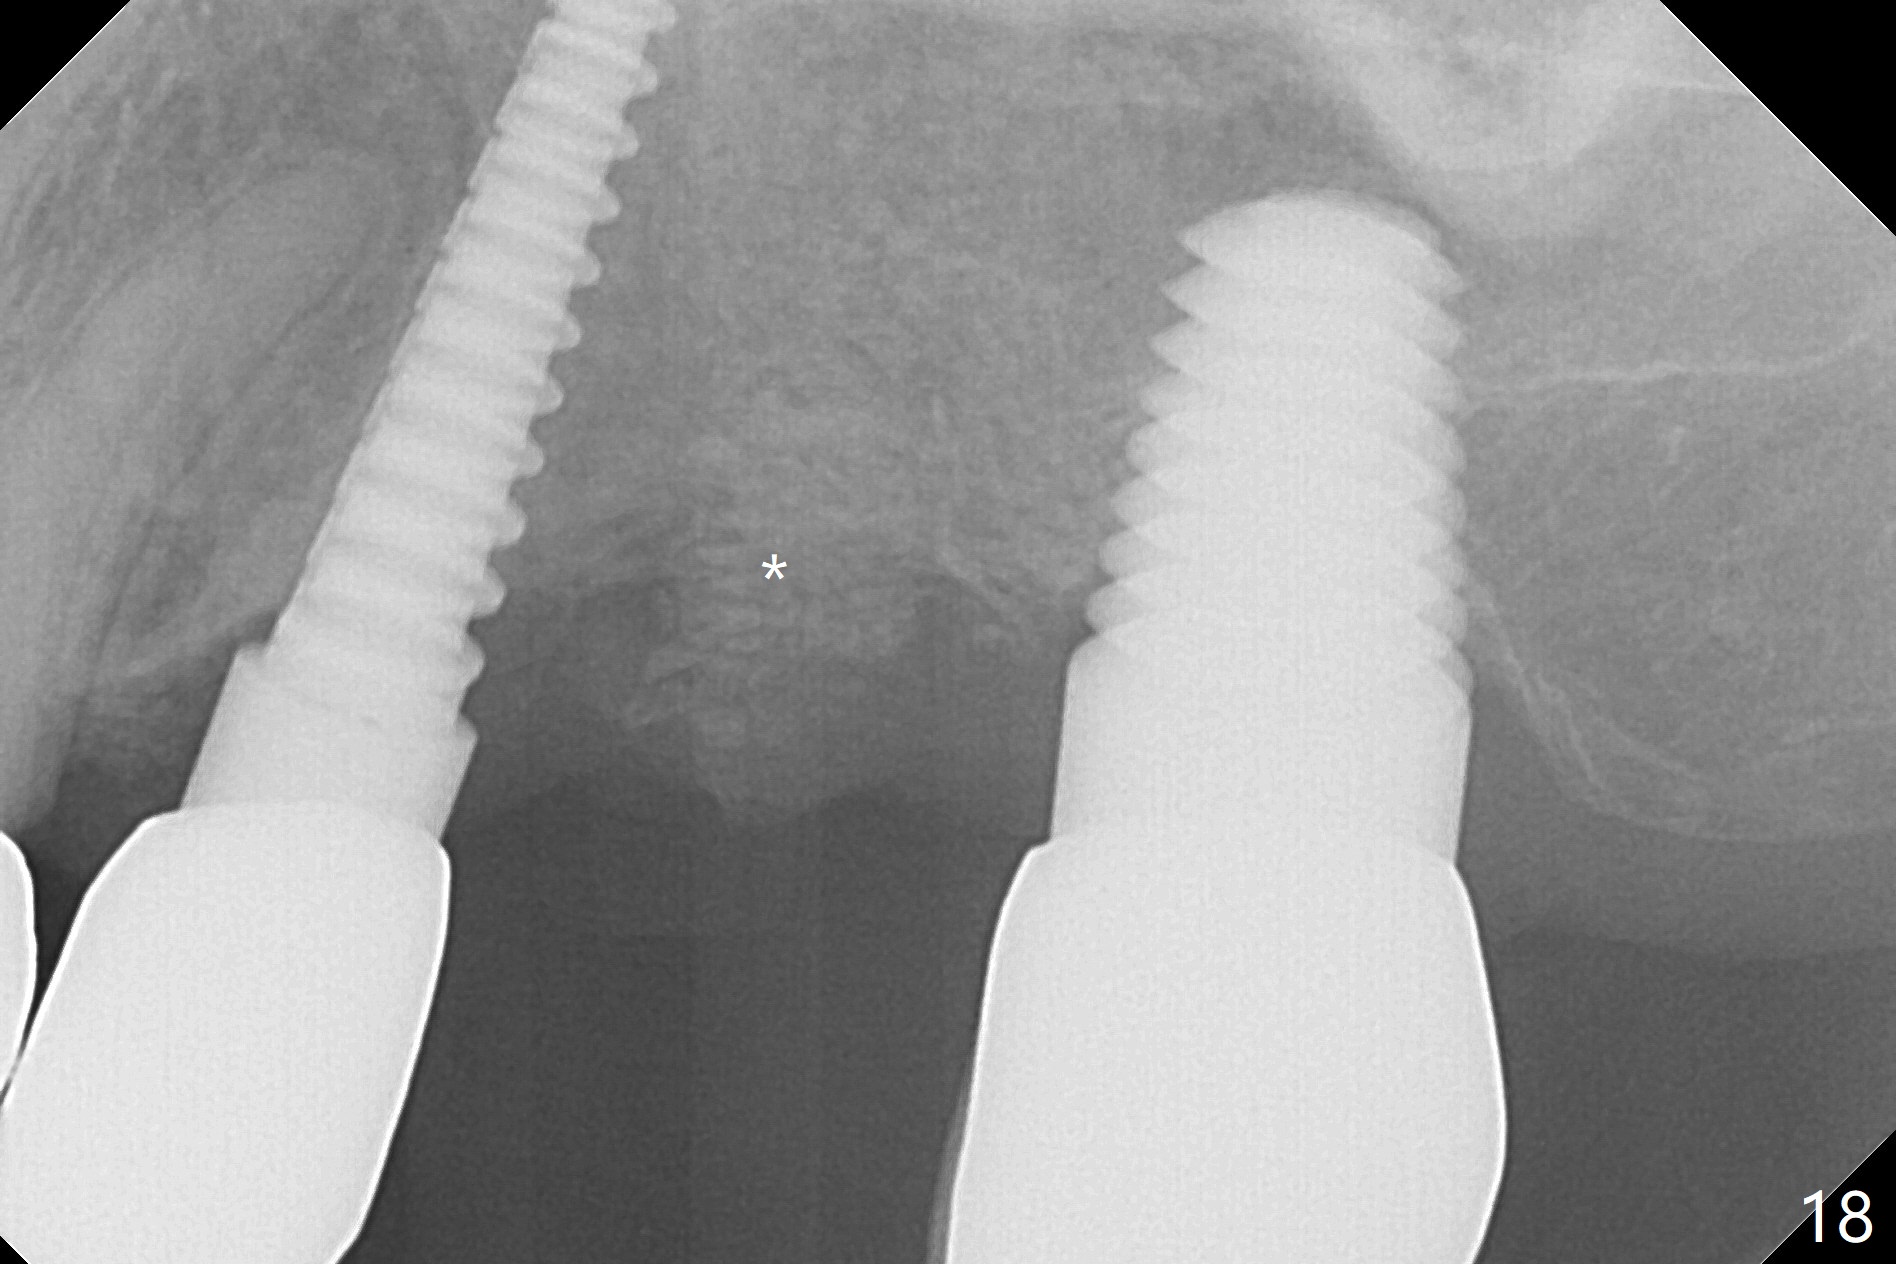

Initial osteotomy in the septum of the tooth #14 is 9 mm, approximately 2 mm from the sinus floor (Fig.1).  Subsequent osteotomy depth is 11 mm, followed by insertion of a 4.5x11 mm dummy implant (Fig.2).  After use of Magic Drill (MD) 4.8 mm for 9 mm, a 5x11 mm IBS implant is placed with sinus lift without additional bone graft (Fig.3 *).  In contrast, autogenous bone (from MD) and Vanilla Graft are meticulously placed in the remaining socket (+) before and after placement of a 6.5x5.7(2) mm abutment.  An immediate provisional is fabricated to close the sockets.  There is buccal tenderness 1-3 months postop.  There is distopalatal implant thread exposure.  A healing abutment (5.5x2 mm) is placed.  CT confirms thin buccal plate (Fig.4,5).  It appears that the implant should have been as palatal as possible.  The tenderness remains for the next 2 weeks.  When the healing abutment is removed, the implant seems to have been placed shallow, ~ 1 mm subgingival (Fig.6).  With local anesthesia, the implant is reversed to clean the coronal threads with Titanium brush and copious irrigation (Fig.7).  The implant is then placed ~4 mm subgingival (Fig.8) and slightly subcrestal (Fig.9,10).  It appears that the postop bone loss (Fig.9 *, as compared Fig.1,2) makes the implant look to be placed too shallow.  When the implant is being placed deeper, the buccal plate feels intact.  The early periimplantitis is apparently due to postop bone loss more than buccal placement, although certain degree of buccal bone resorption must occur.  A 6x4 mm healing abutment is placed.  Left facial swelling develops 2 days post implant elevation (Fig.11,12, as compared to preop (Fig.13)).  The left maxillary sinus cloud (Fig.12) appears to be a false positive finding, since the same feature exists prior to implant elevation (Fig.13).  Both sinuses look clear prior to implant elevation (Fig.14).  Amoxicillin switches to Augmentin and Flagyl, since the patient is reluctant to have the implant removed.  Finally the sinus infection is under control.  The patient feels left facial swelling 9 months postop (5 months post elevation) and reports left nasal discharge ~ 1 month earlier.  There is mild buccal plate tenderness.  The implant seems to be buccally placed (Fig.15,16), although there is no significant change radiographically (Fig.17).  The implant is removed with bone graft (Fig.18 *).  To avoid complication and failure, an immediate implant at the upper 1st molar should be short and placed deep.